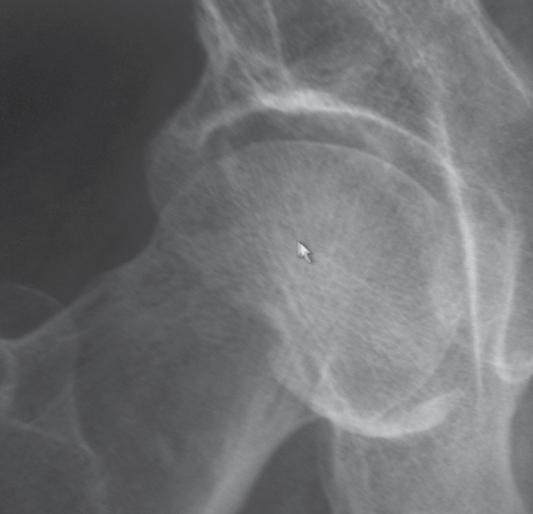

a. Vad är en s k CAM-lesion? (1p)

b. Vilka symtom kan en patient ha med en sådan lesion? (1p)

c. Vilka är de röntgenologiska undersökningsfynden? (1p)

a. CAM-lesion kan vara en orsak till femuroacetabulär impingement (FAI) där man har en påbyggnad på collum femoris främre övre omfång.

b. Symtom kan vara höftsmärta och inskränkt rörlighet, ssk flexion men även inåtrotation och adduktion.

c. På slätröntgen eller CT, alternativt MR ses ”Pistol-grepps-deformitet”, benpåbyggnad vid övergång superiort mellan caput-collum och förlust av sfäriciteten av caput femoris.